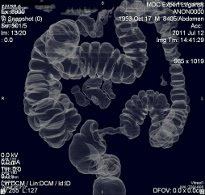

Метод неинвазивного исследования толстого кишечника, основанный на его визуализации с использованием возможностей современной рентгеновской мультиспиральной компьютерной томографии. Это особый вид компьютерной томографии, при которой исследуется толстая кишка. Обычная колоноскопия (не виртуальная) - это эндоскопический метод диагностики, при котором эндоскоп вводится в кишку непосредственно.

Исследования проводятся на компьютерном томографе Toshiba AQUILION 128 срезов с применением газового инсуфлятора Ulrich Medical